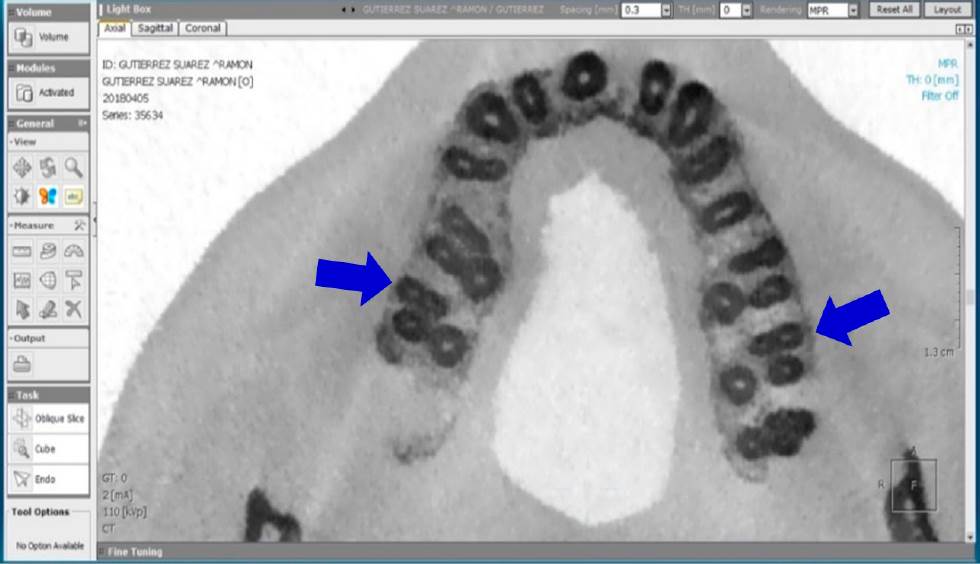

Se realizó el análisis de CBCT a cada diente para confirmar la presencia o ausencia del conducto MV2. Se usó la misma computadora con lector de CD y el programa OnDemand3DTM (Cybermed Inc., Daejeon, Korea). Se consideró presente el conducto, cuando al analizar la imagen tomográfica de la raíz mesial en un corte axial de 0.3mm, desde el piso de la cámara pulpar hasta el ápice, se observara un punto adjunto al conducto MV1, con una trayectoria continua a partir del piso pulpar del conducto hasta el tercio medio como mínimo, en la vista axial (Figura 1-3).

Figura 2 Corte tomográfico desde una vista axial, las flechas señalan un segundo molar maxilar izquierdo y uno derecho con presencia de conducto MV2 en la raíz mesiovestibular.